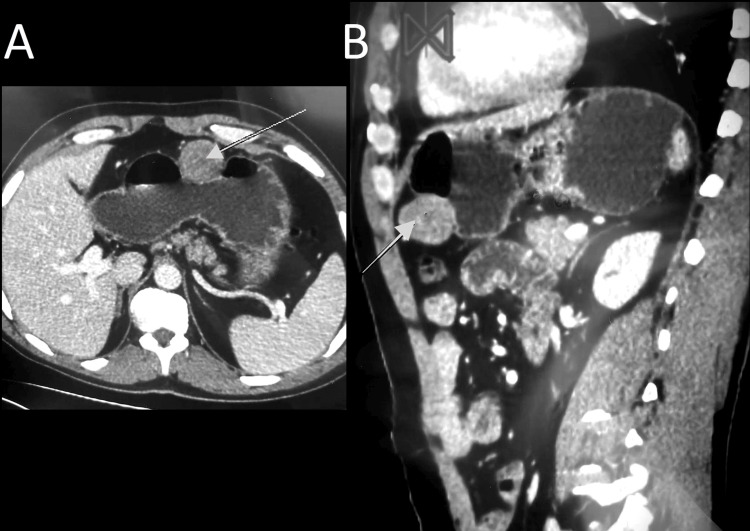

Abdominopelvic computed tomography (CT) scan revealed a homogenous and enhanced vascular mass that arose from a splanchnic branch; it was adjacent to the anastomosis performed before, suggesting a pseudoaneurysm of the GDA (Figure 1A, 1B).